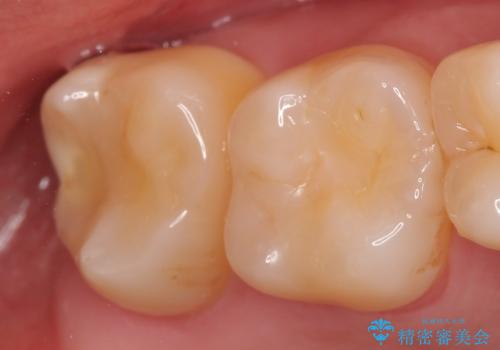

- 右上7の虫歯が大きく、他院にて抜歯と言われたが、なんとか残せないかと当院にいらっしゃった方の症例です。

自発痛の既往および持続痛を認めたため、カリエス除去後根管治療を行いました。

その後オールセラミッククラウンによる補綴を行いました。